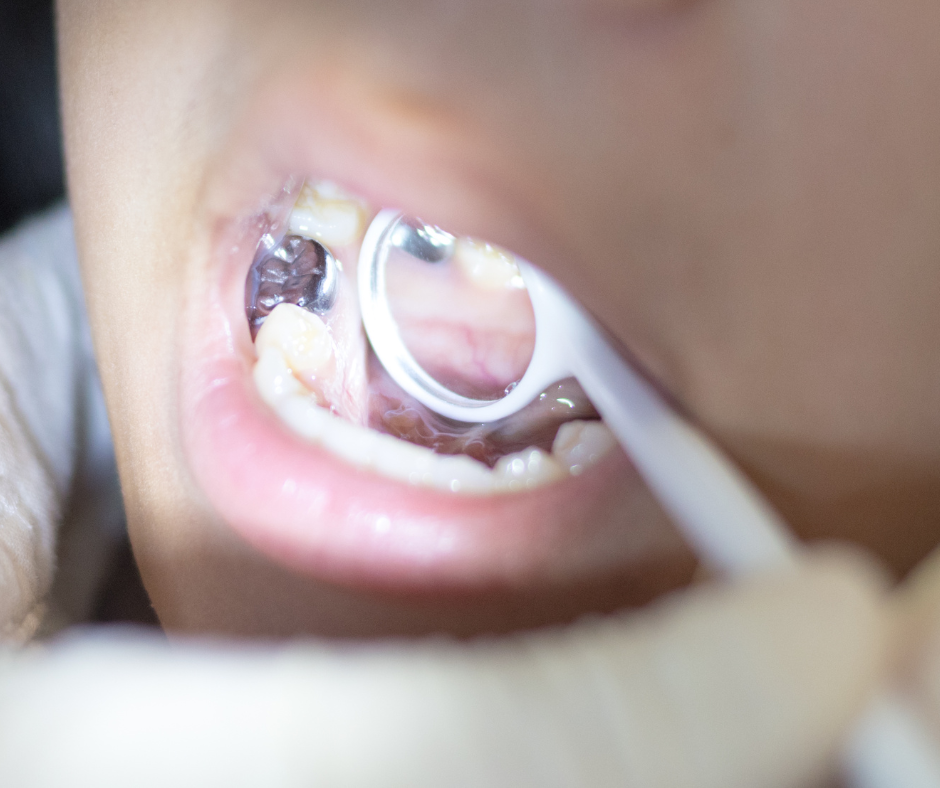

Sealants serve as a proactive measure to shield your teeth from potential decay, particularly targeting the occlusal or chewing surfaces. The back teeth, or posterior teeth, naturally exhibit pits and fissures, creating crevices for bacteria and microscopic food remnants. These sealants are essentially resin coatings applied to these crevices, acting as a barrier against decay by hindering the accumulation of bacteria and debris in these otherwise challenging-to-clean regions.